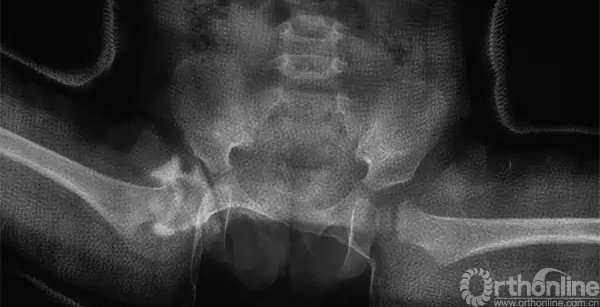

病例介绍:17个月女孩,因“步态异常”拍片发现右髋脱位。发育良好,无早产。体重10kg,家长诉偶尔可感到孩子“右髋部有响声”,否认家族髋关节疾患相关病史。查体:可独立行走,行走跛行。屈髋外展受限,Allis征阳性。入院后拍“骨盆正位片”及“双髋关节核磁”。行右下肢皮肤牵引10天,孩子配合皮肤牵引稍差。各项术前常规检查无手术禁忌,静吸复合麻醉下行“右髋脱位关节造影、试行闭合复位、人类位石膏裤固定”。

行右髋关节造影,维持屈髋100°、外展50°位时造影分析“复位质量”:股骨头内侧缘与坐骨体相重叠,股骨头覆盖率(FHC)为46.2%,“盂唇软骨复合体”形成的造影充盈缺损区位于股骨头外上方,股骨头没有明显下移,认为“头臼对位关系满意”。

根据对“复位稳定性”及“头臼对位关系”的判断,术中判断“复位可以接受”,行“人类位石膏裤”(human position spica cast)固定。石膏固定后拍片示“头臼对位关系满意”。